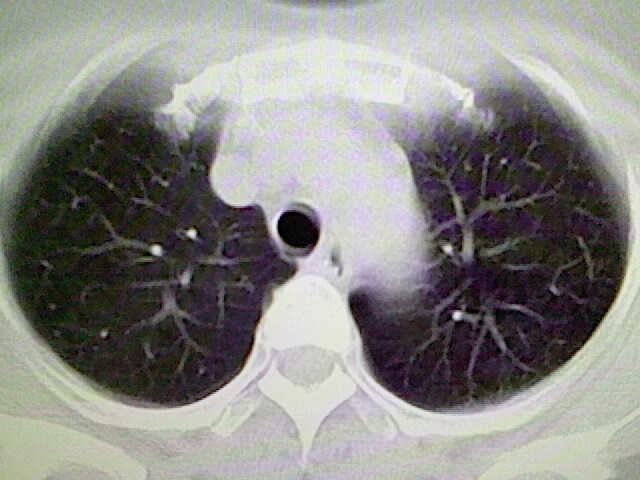

女,52岁,咳嗽,咳痰多日

左下肺陈旧纤维索条!

左肺舌段炎性改变

左肺上叶下舌段炎症并局部胸膜反应。

左肺舌段炎性反应。片子的质量太不好了。